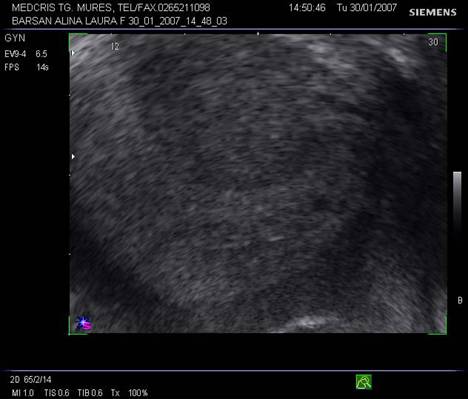

Fig nr 54 In sacul gestational ectopic se evidentiaza vezicula vitelina, ecou discret hiperecogen rotund

Fig nr 55 Langa ovarul stang, o formatiune ovalara ( intre calipere ) de 18 mm, cu ecou hipoecogenic central, la 6 sapt.de amnoree

![]()

Fig nr56 Aceeasi

pacienta,ca in figura precedenta, la

aproape 8 sapt de amenoree, retrouterin cu o formatiune inomogena ( cu sageata

), care intraoperator se dovedeste o sarcina extrauterina necomplicata

pavilionara tubara stg.